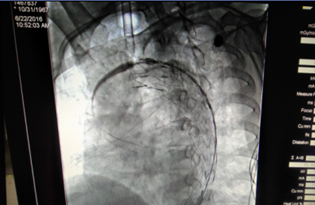

我院外二科主治醫(yī)師魏宇(左二)

正在為患者施行主動脈夾層腔內(nèi)修復(fù)術(shù)

術(shù)中(釋放支架)